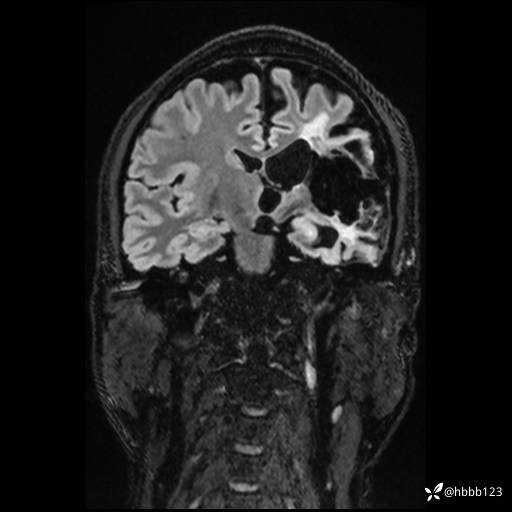

CUBE FLAIR冠状位: